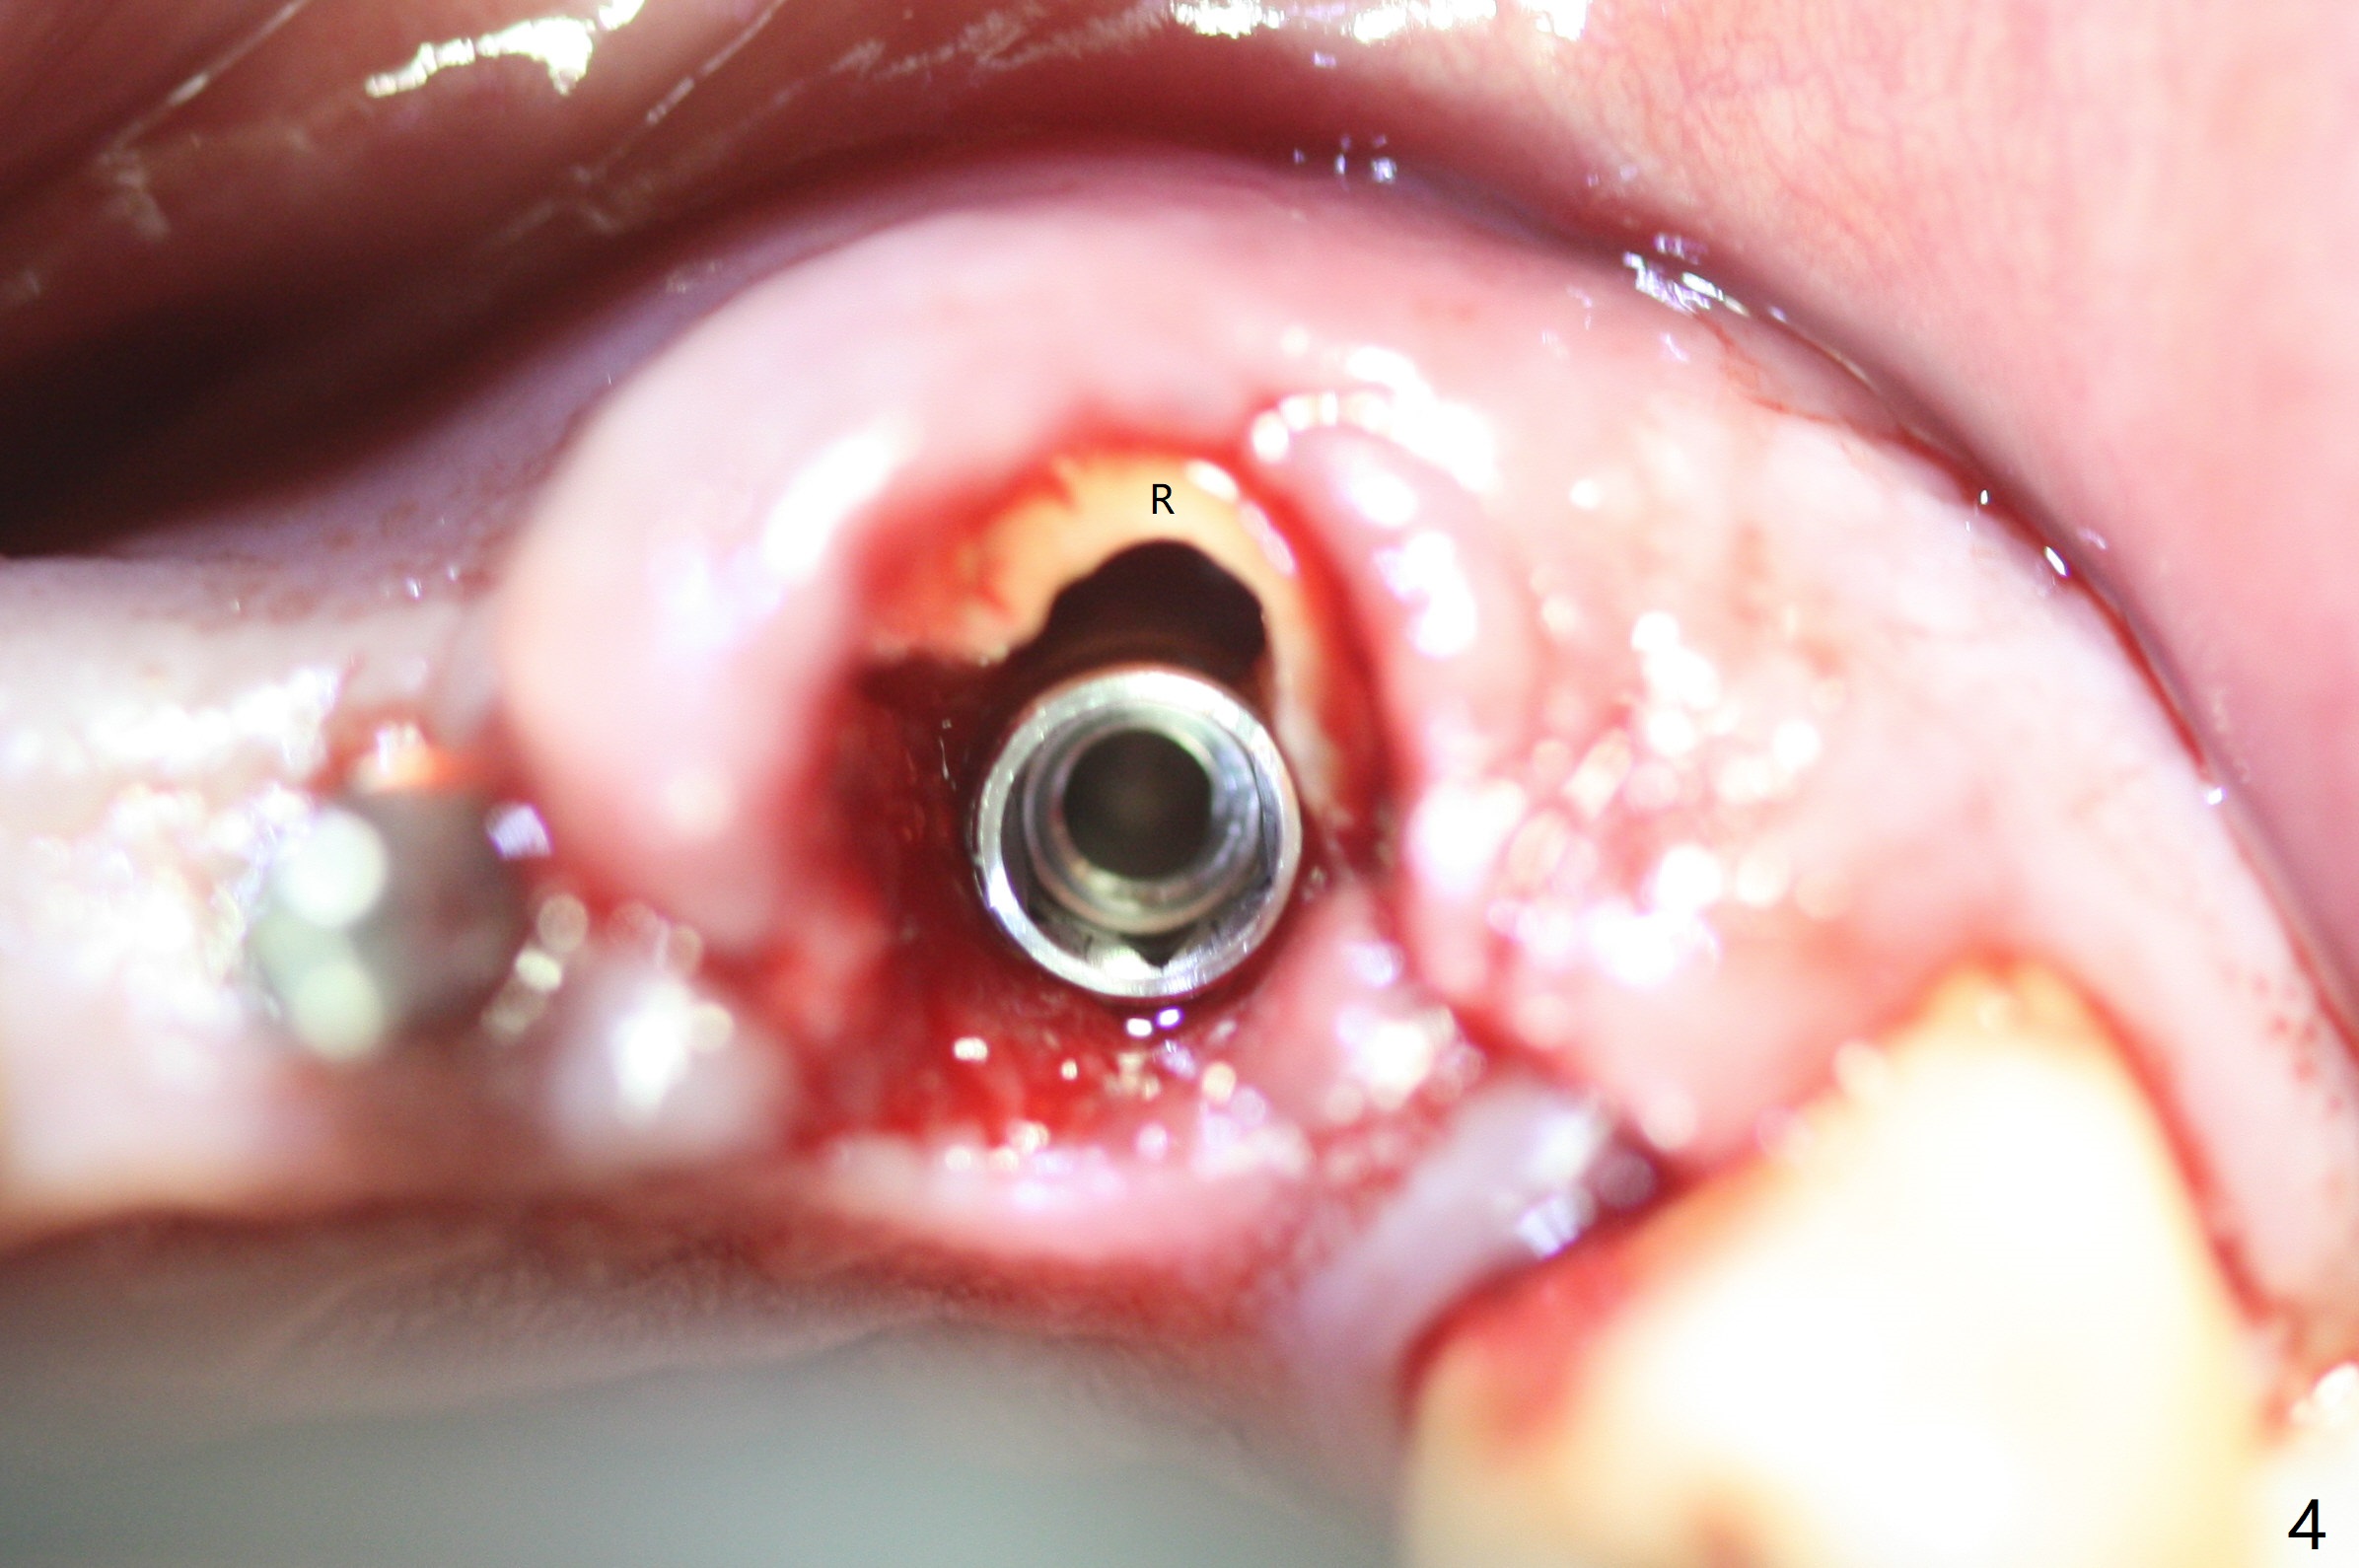

The buccal plate at #10 undergoes atrophy 9 months post immediate implant (Fig.1 *). To prevent the same post-extraction complication at #11, a technique called socket shield is going to be adopted. The buccal portion of the root (Fig.2-6 R, half-moon shaped) remains in place while a 3.5x13 mm implant is placed in the palatal portion of the socket (>50 Ncm). In fact the root is trimmed slightly subcrestal (Fig.6 C). It is assumed that there will be no or minimal bone resorption as long as the periosteum between the buccal plate and the remaining buccal root is not disturbed after tooth removal. After placement of a 4.5x15 degrees A (2mm) angled abutment and Vanilla graft (Fig.7 *), an immediate provisional is fabricated (using a central incisor crown form for #10 because of extra wide space of #11, Fig.8). There is no buccal plate atrophy at the canine 11 days postop (Fig.9). There is smooth transition from the grafted bone to the native bone 4.5 months postop (Fig.10). The buccal plate remains non-atrophic at the canine 4.5 months postop (Fig.11,12). CT taken 1 month post cementation shows that the implants at #10 and 11 are placed somewhat lingually (Fig.13,14 L (*: socket shield)). Gingival swelling is noted (Fig.15 *) with +Bleeding On Probing (^) 8 months post cementation (at the time of #21/24 impression). It appears that the socket shield (Fig.16 S) causes infection and loss of bone graft (*). The shield will be removed with an oblique accessory incision to save the papilla between #10 and 11 (Fig.17 black line). Prepare PRF for sticky bone (x1).